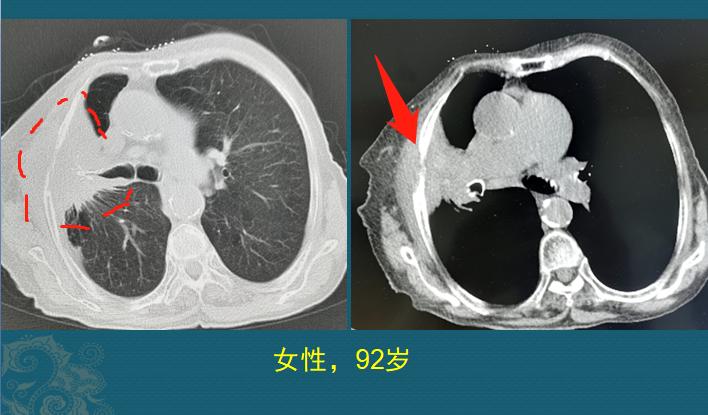

病例1,女性,92岁

这位老人右侧胸痛10个月,上了年轻的老人,难免有点头疼脑热,没在意,直到这几天疼得厉害,睡不着觉了,结果CT发现晚期肺癌(左图红线区):

这个肺癌已经是晚期了,右图红箭头所示,癌细胞吃掉了半根肋骨(白色的是肋骨),变细了,老人的胸痛跟胸膜和肋骨侵犯有关。

这种情况也不建议过度治疗了,以止痛为主,一切原则是让老人少遭罪。